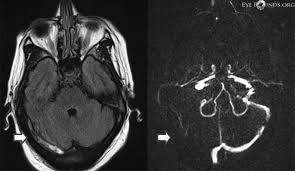

The Radiology Assistant Cerebral Venous Thrombosis

The Radiology Assistant Cerebral Venous Thrombosis from radiologyassistant.nl

Cerebral venous sinus thrombosis occurs when a blood clot forms in the brain's venous sinuses. The diagnosis of cvst needs high threshold for suspicion, especially in patients with meningitis or. Prognosis of cerebral vein and dural sinus thrombosis: You may also need to take part in a special rehab program or physical therapy if you. It is a difficult diagnosis because of its nonspecific clinical presentation and subtle imaging findings. It is more common than previously thought and frequently missed on initial imaging. † intracranial hemorrhage that occurred as the consequence of cvst is not a contraindication for anticoagulation. We received 32 patients hospitalized on. How is cerebral venous sinus thrombosis diagnosed? Severe dehydration after competitive sport had induced cvst. Cerebral venous sinus thrombosis (cvst) is a clot in the venous drainage system of the brain and can present to ophthalmology. A statement for healthcare professionals from the american heart association/american stroke association. For this reason, it seems to be overlooked not only by general practitioners but also in some specific cases by neurologists as well.1.

Because of the generally good prognosis and variable clinical signs. It is a difficult diagnosis because of its nonspecific clinical presentation and subtle imaging findings. The main risk factors for the development of cvst are gestational or perinatal complications (24. Cvst indicates cerebral venous and sinus thrombosis; While the patient's headache initially responded to pain medication. Prognosis of cerebral vein and dural sinus thrombosis: Cerebral venous sinus thrombosis (cvst) is the presence of a blood clot in the dural venous sinuses, which drain blood from the brain. Die thrombosen der intrakraniellen venen und sinus, stuttgart, 1965; Lmwh, low molecular weight heparin; Cvt is a rare condition (~1% of all strokes). Cvst clinically presents with headache, often associated with nausea, vomiting, conscious disturbances, and sometimes with eyelid oedema, blurred vision or diplopia, and seizures. Two patients presented with cerebral venous sinus thrombosis (cvst) associated with iron deficiency. The initial head ct was negative.